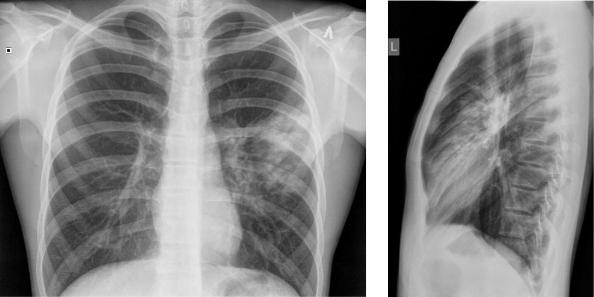

Медицинская тема: легочные осложнения при пневмонии